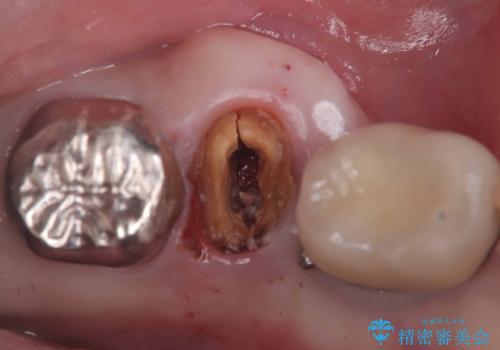

【1Dayインプラント治療! 低侵襲で短期間での治療】 咬むと歯が痛い! 歯根破折